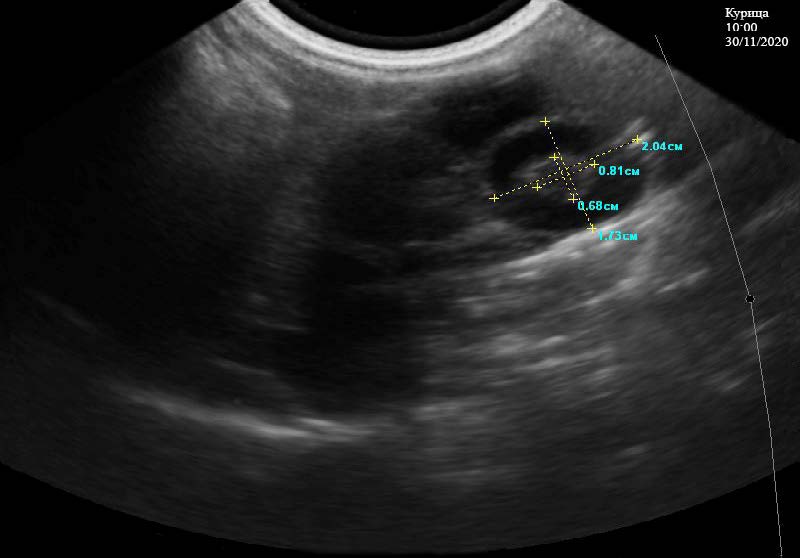

При ультразвуковом исследовании почек у курицы отмечается, что их границы ровные, четкие. Эхоструктура кортикального и мозгового слоев в срединной плоскости неоднородная, эхогенность паренхимы соответствует норме. Капсула не визуализируется. Отчетливо видно наличие более светлых и темных участков в паренхиме, что связано с фильтрацией минеральных веществ, содержащихся в крови. Мочеточники на всем протяжении не визуализируются. Общая длина почек составляет 4,70 см (рис. 1). Ультразвуковое исследование половых органов у курицы кросса Хайсекс белый проводилось в несколько этапов: Начало первого этапа проводили в 9:35 часов 30.11.2020 г. Отмечено наличие созревшего фолликула, который попадает в воронку. Выявляются локализованные объемные образования округлой формы – фолликулы, находящиеся на разных стадиях развития, размерами 0,96*0,99, 1,82*1,97, 0,57*0,70 см (рис. 2). Они имеют однородную эхогенность и эхоструктуру гиперэхоогенного характера, дающие слабую акустическую тень. Вокруг них визуализируется несколько мелких фолликулов, состояние границ между ними четкое просматривается, наличия артефактов не отмечено.

Рис. 2. Фолликулы на разных стадий развития в яичнике у курицы кросс «Хайсекс белый». 9:35 ч. 30.11.2020 г.

Второй этап исследования осуществляли в 10:00 30.11.2020 г. Отмечается желток, покрытый вителлиновой оболочкой, который расположен в центральной части белкового отдела яйцевода имеет размеры 0,81*0,68 см, большую плотность и хорошую эхогенность. На его периферии расположено небольшое количество белка 1,73*2,04 см с более низкой плотностью. При этом, на снимке отмечается хорошо контурированный черный диск (рис. 3).

Рис. 3. Краниальная часть белкового отдела у курицы кросс «Хайсекс белый», с наличием желтка с оболочками. 10:00 ч. 30.11.2020 г.